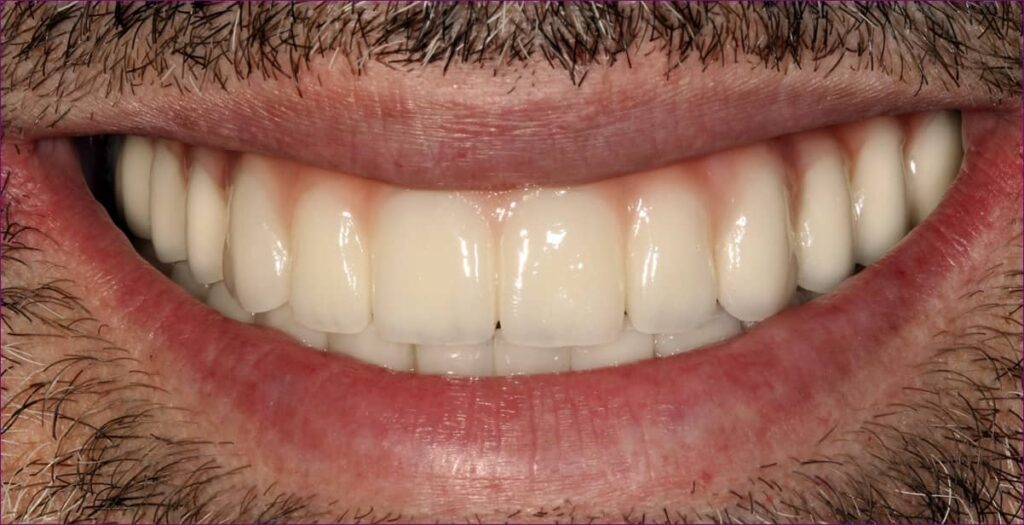

Az elkészült pótlás

A becsavarozott, átadott alsó-felső rögzített pótlás röntgenfelvétele az alább látható.

Páciensünk a kezelés során végig együttműködő és türelmes volt, a végeredménnyel pedig maximálisan elégedett volt.

Boldog mosolyán mindez vissza is tükröződik!